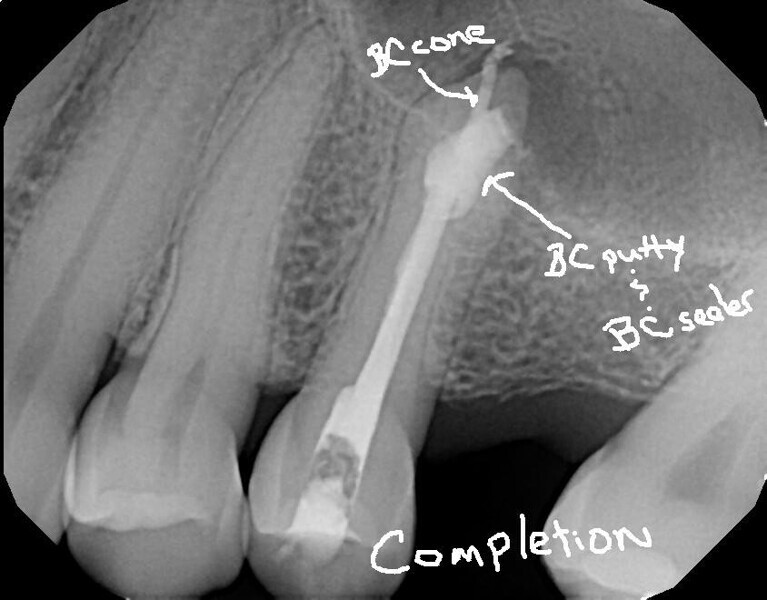

Fig. 16a: Case treated with a Bioceramic master cone, sealer and putty. Note the excellent apical control in this blunderbuss apex. (Courtesy of Dr. Rico Short)

Fig. 16b: Case treated with a Bioceramic master cone, sealer and putty. Note the excellent apical control in this blunderbuss apex. (Courtesy of Dr. Rico Short)